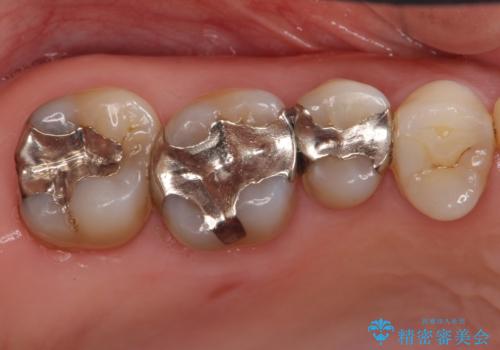

銀歯を白く 虫歯治療

- 虫歯治療を希望して来院。

保険適用の銀色のつめもののやり替えを行いました。

- 30.8万円(右上4567 emaxプレスインレー 7万円x4本)費用は治療当時の料金となります